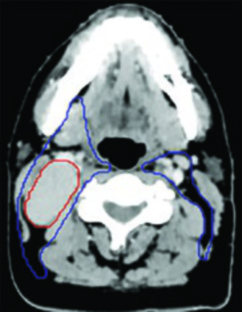

Paciente con carcinoma nasofaríngeo no queratinizante, EBV positivo, estadio T1N1. La RM mostró un tumor confinado a la nasofaringe sin extensión parafaríngea significativa. La PET/CT confirmó un ganglio patológico en niveles II y III derechos. El GTV70 primario se limitó al tumor visible en la fusión TC-RM, con un CTV70 de expansión 3 mm. El CTV subclínico incluyó la nasofaringe completa, la mitad del seno esfenoidal, un tercio del clivus, la fosa pterigopalatina bilateral y los niveles ganglionares IB a V bilaterales con ganglios retrofaríngeos.